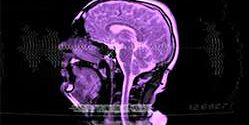

O vídeo do cantor Sivu mostra o interior da cabeça humana no processo da fala e canto

Quantas vezes você já pensou em querer entrar na mente de um músico? O cantor Sivu tentou realizar esse desejo para os fãs: seu novo clipe, da música “Better Man Than He”, foi filmado com a ajuda de um aparelho de ressonância magnética.

A ideia surgiu da obsessão do artista de capturar imagens sem usar câmeras e lentes convencionais. Para não perder a essência das imagens do aparelho médico, não houve muita modificação na pós-produção do clipe, deixando o conceito básico ainda mais impressionante.

Sivu também tirou a inspiração de um fato importante: pesquisas feitas para melhorar o tratamento de crianças que nascem com lábio leporino e fenda palatina. O clipe foi produzido no Hospital St Basrtholomews, principal centro das pesquisas da doença.